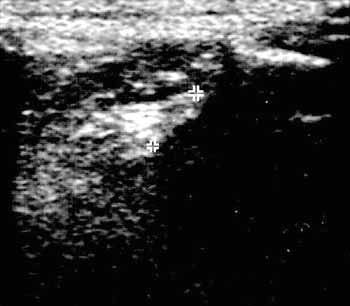

Ультразвуковая диагностика поражений коленного сустава.

Рис. 5. Лигаментоз передней крестовидной связки (+).

Новости лучевой диагностики 2002 1-2: 48-51